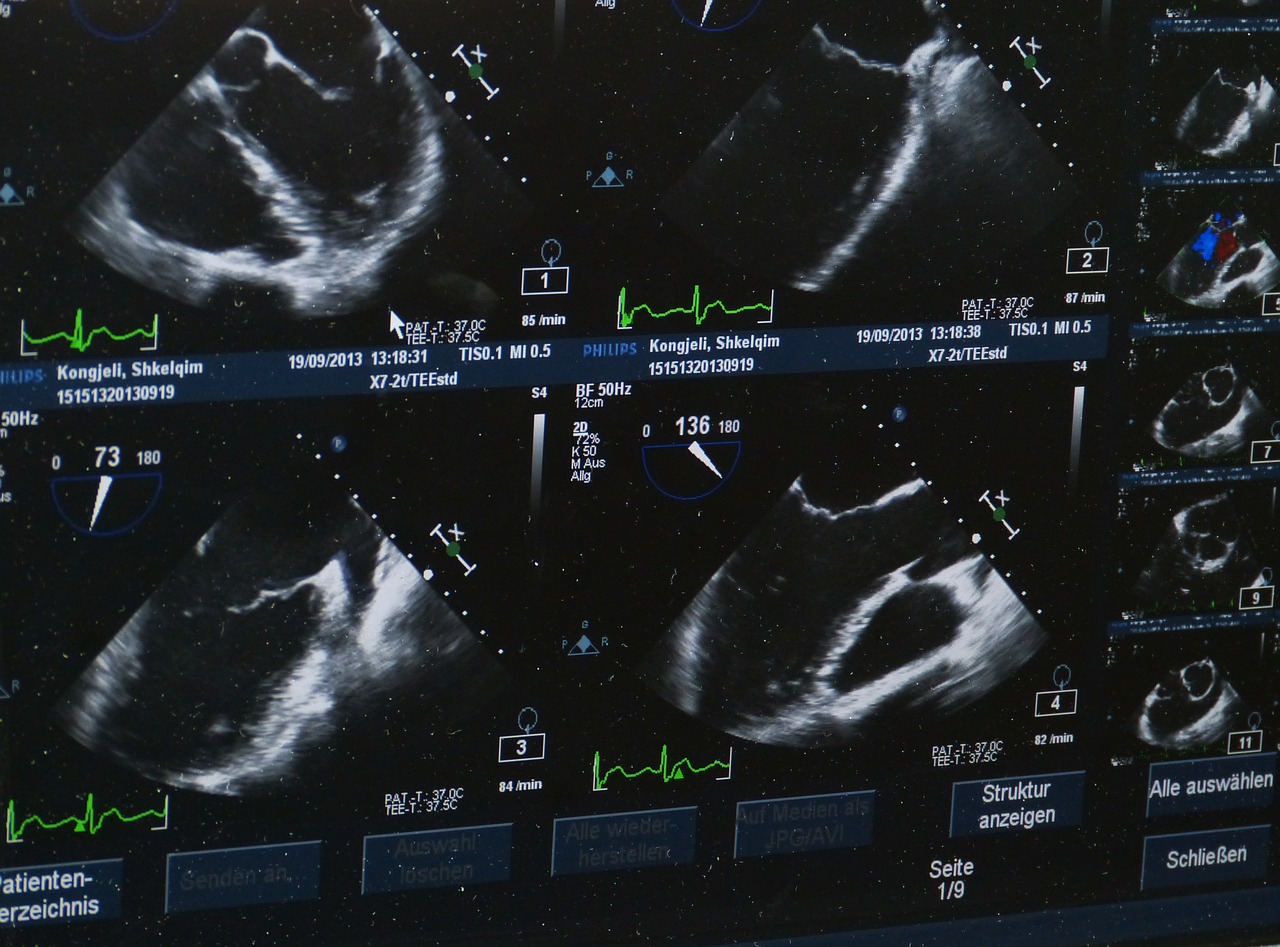

Ako žena počne da oseća jake bolove u stomaku, nema menstruaciju, a povremeno krvari, stručnjaci savetuju da podhitno ode ginekologu. Lekari tada osim obaveznih testova krvi, obavljaju pregled ultrazvukom, kako karlice, tako i stomaka. Nažalost, neke dame ne prepoznaju opasnost, pa završe na odeljenju Hitne pomoći.